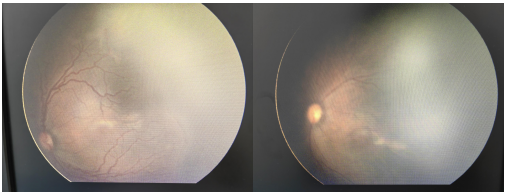

该患儿属于超早早产儿、超低出生体重儿,全身情况复杂、生命体征不稳定,视网膜发育问题尤为突出。在近期新生儿数字化广域眼底成像系统(RetCam3)广角眼底照相筛查中,眼科医生发现其眼底出现典型病变,确诊为“早产儿视网膜病变(ROP)Ⅰ区3期Plus(+)”。该类型病变进展迅速,如不及时干预,极易引发牵拉性视网膜脱离、永久性失明等不可逆损伤,治疗时间极为紧迫。

术中,眼科手术团队操作精细、配合默契,术后患儿恢复良好,经密切复查显示,眼底病变已得到有效控制,首次治疗即取得显著成效。

(手术前后对比)